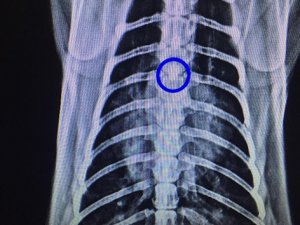

Ameliyata alınan kedinin soluk borusundan 1,5 santimlik taş çıkarıldı.

Zonguldak Veteriner Kliniğinde röntgeni çekilen kedinin soluk borusunda 1,5 santimlik taş olduğu tespit edildi. Veteriner hekimler Önder Alkan ve Suat Ulucak tarafından 4 saat süren ameliyatla kedinin soluk borusundaki taş çıkarıldı. Yoğun bakıma alınan kedinin durumunun iyi olduğu öğrenildi.

Veteriner Hekim Önder Alkan, ''Dün akşam Kastamonu ilinden geldi bize hastamız. Yaptığımız tetkiklerde soluk borusunda yabancı cisim tespit ettik akciğerin giriş bölgesindeydi kalbin üzerinde kötü bir solunumu vardı boğulmak üzereydi. Açık bir ameliyat geçirdi. Soluk borusundan bir taş çıktı. Zorlu bir ameliyattı 6 saat sürdü.

Ameliyattan sonra solunumu düzeldi. Akciğerler düzeldi 3 günlük sıkıntılı bir durumu var. Oynarken muhtemelen oldu aşağıya kadar indi. Bir anda solunum güçlüğünden dolayı anlamış vatandaş ve hemen veterinere getiriyor ve yapılan tetkiklerde yabancı cisim görülüyor.

Bu ameliyat için otomatik solumun sistemi gerekiyor. Bu sistem olan yerlerde bu ameliyatlar yapılıyor. Zor ve riskli bir ameliyat” şeklinde konuştu.